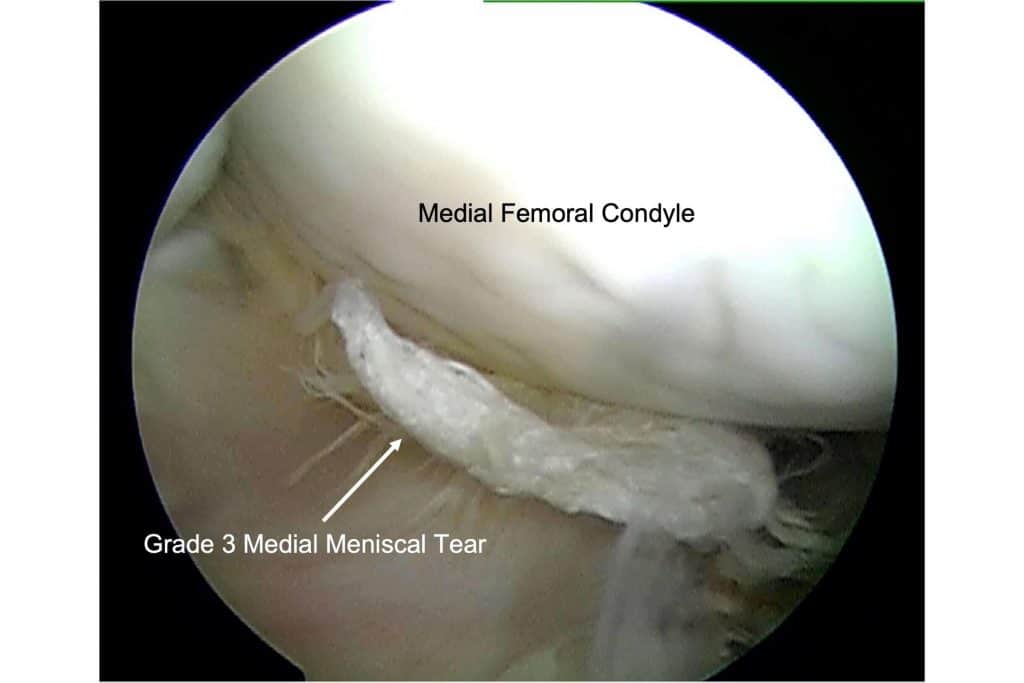

Equine Meniscal Injuries

Equine meniscal injuries can cause severe pain and lameness, but if diagnosed and treated properly many horses can return to work.

Find out how to get athletic horses with injuries to the large, complex stifle joint on the road to recovery.